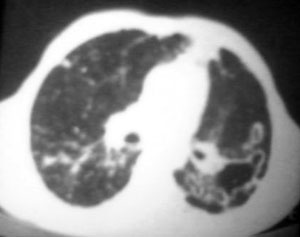

以下是引用逸风在2006-9-12 14:57:00的发言:[br]ct显示双肺上叶点片状及纤维索条状密度不均影,肺野外带近胸膜可见大小不等的含气空腔,壁略厚,境界清晰,未见液平面,中下肺野散在小片状及点状高密度影;纵隔内显示点状钙化,未见明显淋巴结肿大,构成胸廓诸骨未见明显异常.[br]诊断意见:1.双肺结核合并支气管播散;2.双肺上肺大泡.